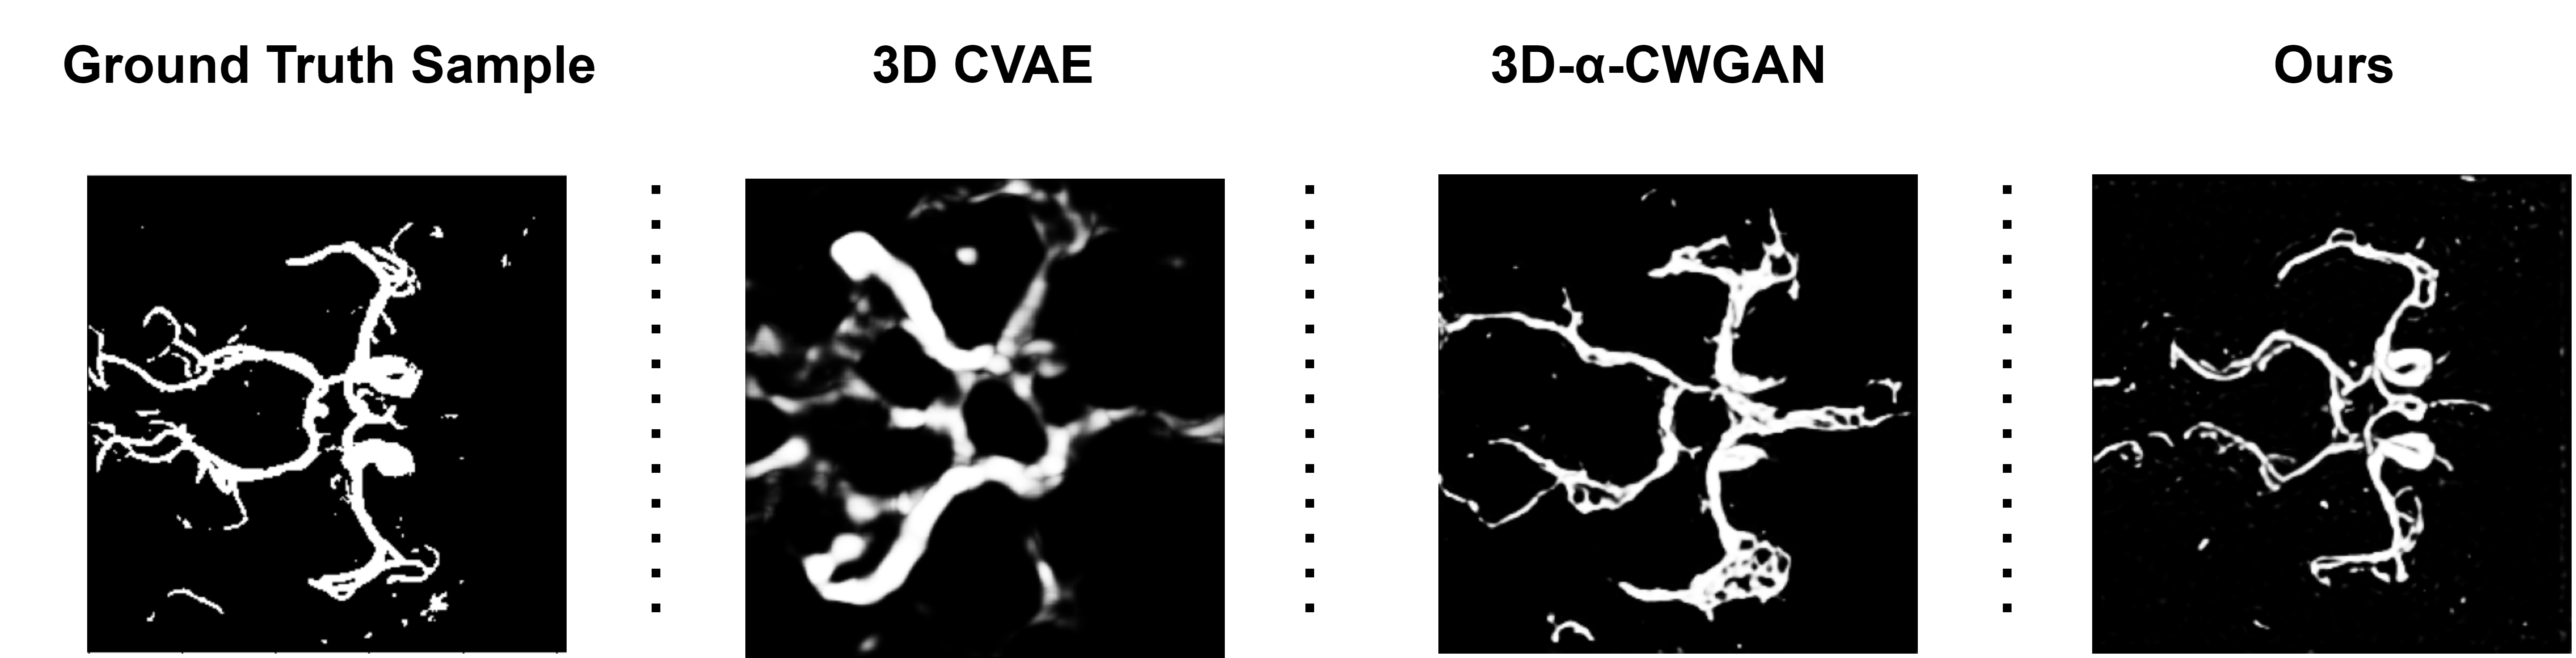

Results and Discussion. To assess the performance of our model, we compared it against two established conditional generative models: 3D C-VAE [13] and a 3D-α𝛼\alpha-WGAN [14] along with a vanilla LDM and an LDM with shape guidance. We use the FID score to measure the realism of the generated vasculature. To calculate FID we used a pre-trained InceptionV3 as a feature extractor. A lower FID score indicates higher perceptual image quality. In addition, we used MS-SSIM and 4-G-R SSIM to measure the quality of the generated images [15, 21]. MS-SSIM and 4-G-R SSIM are commonly used to assess the quality of synthesised images. Typically, a higher score is indicative of better image quality, implying a closer resemblance between the synthesised CoW and the ground truth reference. MS-SSIM and 4-G-R SSIM were calculated over 60 synthesised CoW cases for each model. Table 1 presents the evaluation scores achieved by our model, 3D CVAE, and the 3D-α𝛼\alpha-WGAN and the above metrics. As seen in Table 1, our model demonstrates a better FID score, suggesting that the distribution of CoW variants synthesised by our model is closer to that observed in real CoW data, compared to the other models. Additionally, our model achieves higher MS-SSIM and 4-G-R SSIM scores compared to the other methods. These higher scores indicate better image quality, implying that the generated CoW samples resemble the real CoW images more closely. Fig. 3 provides a qualitative comparison among the generated samples obtained from the three models to provide additional context to the quantitative results presented in Table 1. As the output of each model is a 3D vascular structure, maximum intensity projections (MIP) over the Z-axis which condense the volumetric representation into a 2D plane are used to visually compare the synthesised images.

Refer to caption

Figure 3: Comparison between the maximum intensity projections (MIPs) of a real Circle of Willis(CoW) against those synthesised with 3D CVAE, 3D-α𝛼\alpha-WGAN, and our model.

Fig. 3 reveals that the 3D CVAE model can only generate a limited number of major vessels with limited details. On the other hand, although the 3D-α𝛼\alpha-WGAN model produces the overall structure of the CoW, it exhibits significant anatomical discrepancies with the presence of numerous phantom vessels. On the contrary, our model demonstrates a faithful synthesis of the majority of CoW, with most vessels identifiable. To generate variations of the CoW based on the presence or absence of the posterior communicating artery, our latent diffusion model uses class-conditional inputs where the classes represent different CoW phenotypes. Consequently, to demonstrate the class-conditional fidelity of the proposed approach, we also evaluate the model’s performance in a class-wise manner. The qualitative performance of our model for different classes, compared to real images belonging to those classes, is shown in Fig. 3